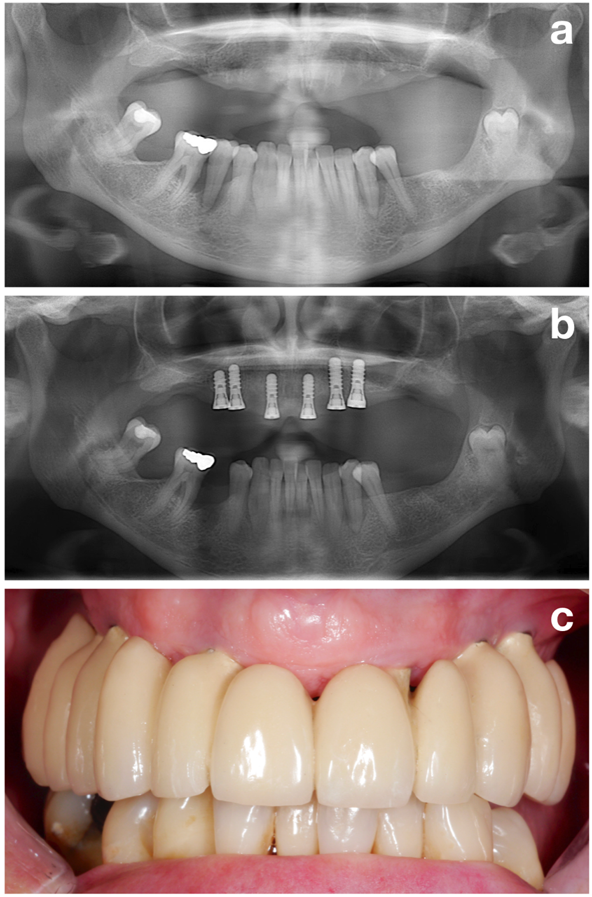

Abbildung 2: Vor der Implantation sollte das Ziel zunächst ein stabiler parodontaler Zustand sein. Patient vor der parodontalen Behandlung (a), nach der parodontalen Behandlung und Implantation (b) und nach der prothetischen Restauration (c). © Dr. K. Bertl

Im ersten Teil (also in der Vorbehandlungsphase) werden alle potenziellen Risikofaktoren ermittelt, um den Patienten bestmöglich auf die spätere Implantation vorzubereiten. Der Fokus liegt dabei jedoch auf einem der wichtigsten Aspekte, nämlich dem Schaffen eines stabilen parodontalen Zustandes (Abbildung 2).